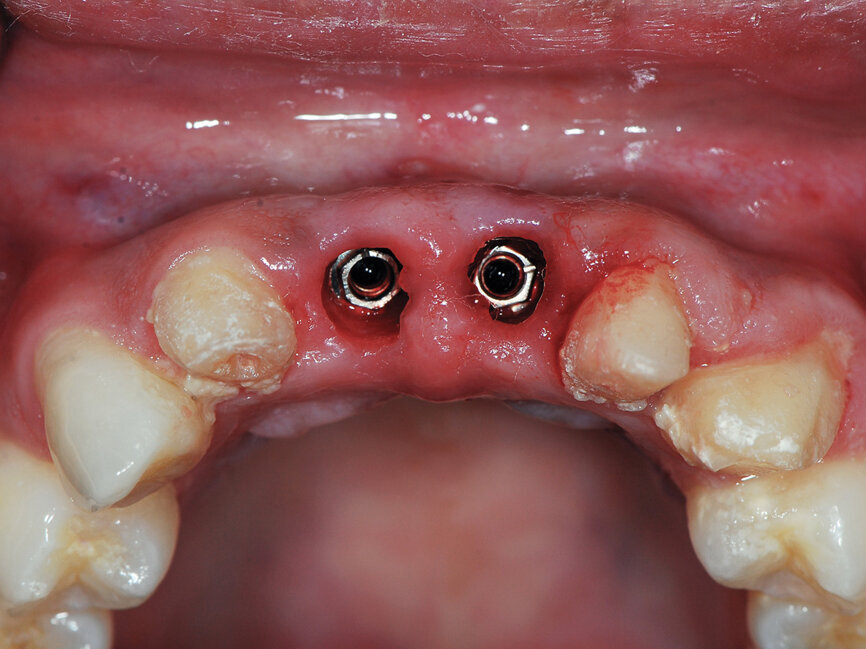

Fig. 8: Picasso Lite+ diode laser removing soft tissue to uncover the implants’ cover screws. (Photo provided by Dr. Gregori M. Kurtzman)

Fig. 9: Uncovery of the implants and healing screws exposed. (Photo provided by Dr. Gregori M. Kurtzman)

Six months post-implant placement, the provisional bridge was removed and preservation of the papillas was confirmed with a natural emergence profile within soft tissue (Figs. 6,7). Local anesthetic was administered. The Picasso Lite+ diode laser was set at 2.5 watts in continuous mode with an initiated tip and at the center of the depression in the soft tissue above the implants cover screw and moved in a circular motion moving outward until the entire cover screw was exposed (Fig. 8).

The process cuts the desired soft tissue and coagulates any bleeding from the cut edges. This was then repeated on the second implant (Fig. 9). Open tray implant impression abutments were placed into the implants and seating verified radiographically. An impression of the maxillary arch was taken utilizing Aquasil heavy body VPS (Dentsply Sirona, Milford, Del.) in a Mira Advanced Implant tray (Hager Worldwide, Hickory, N.C.) and Aquasil Ultra syringed around the preparations and implant abutment heads.